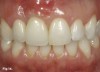

Fig 14. The definitive restoration, a tooth No. 7 crown splinted to implant crown No. 8, shows harmony in regard to the natural dentition as well as the reconstructed gingival architecture, which was improved employing forced orthodontic tooth eruption.

Figure 14